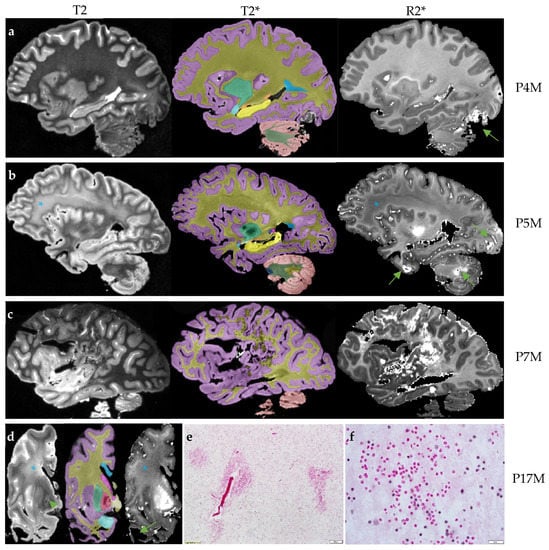

Three FXTAS cases (P4M, P5M, and P7M) exhibited increased R2* consistent with intracranial hemorrhages affecting 2–3 brain regions (Figure 1a–c). One case, P17M, showed absence of the temporal white matter (Figure 1d), which could be caused by hemorrhages. H&E staining of the residual temporal cortex confirmed the presence of numerous small microbleeds with diameters in the order of micrometers (Figure 1e,f) and a large intracranial hemorrhage. None of the control cases showed intracranial hemorrhages. However, as a group, the FXTAS cases did not show significantly increased number of brain regions with intracranial hemorrhages compared with the controls after adjusting for age of death (β = 0.66 ± 0.43, p = 0.14) (Table 2). Ratings of microbleeds were not significantly different between the two groups in the cerebral cortex, deep white matter or cerebellum, after adjusting for age of death (β = −0.78 to 0.27, SE = 0.16 to 0.67, p = 0.06 to 0.62) (Table 2).

Figure 1. The four brains with intracranial hemorrhages. The T2 scan for rating hyperintensities, T2* scan for anatomic segmentation and R2* mapping for rating cerebral microbleeds and estimating R2* transverse relaxation rates are shown for each brain. (a) The R2* mapping of P4M shows an intracranial hemorrhage affecting the occipital lobe and cerebellum (arrow). The T2 scan shows confluent T2-white matter hyperintensities in the adjacent regions while other white matter regions appear to be normal. (b) The R2* mapping of P5M shows intracranial hemorrhages affecting the occipital lobe, anterior temporal lobe and cerebellum (arrows). The frontoparietal white matter shows confluent white matter hyperintensities on the T2 scans and reduced R2* transverse relaxation rate on the R2* mapping (*). (c) The R2* mapping of P7M shows a large intracranial hemorrhage affecting the frontal, parietal and occipital lobes. (d) The scans of P17M show confluent frontal white matter hyperintensities on the T2 scan and loss of iron content on R2* mapping in the same region (*). P17M also shows T2-hyperintensities in the globus pallidus (arrow) and corresponding signal variations on the R2* mapping. All T2, T2* and R2* mapping show the absence of anterior temporal white matter (arrow). (e,f) The hematoxylin and eosin (H&E) staining of the residual temporal cortex of P17M shows numerous free erythrocytes, indications of microbleeds. Scale bar: 100 µm in E and 20 µm in F. On T2* scans, the cerebral cortex is labeled as lilac; cerebral white matter, dark yellow; corpus callosum, blue; caudate nucleus, pink; tail of caudate nucleus, purple; putamen, green; globus pallidus, red; amygdala, light blue; hippocampus, yellow; unnamed subcortical gray matter, vanilla; pons, dark blue; cerebellar cortex, salmon; cerebellar white matter, dark green; and cerebellar dentate nucleus, sand.